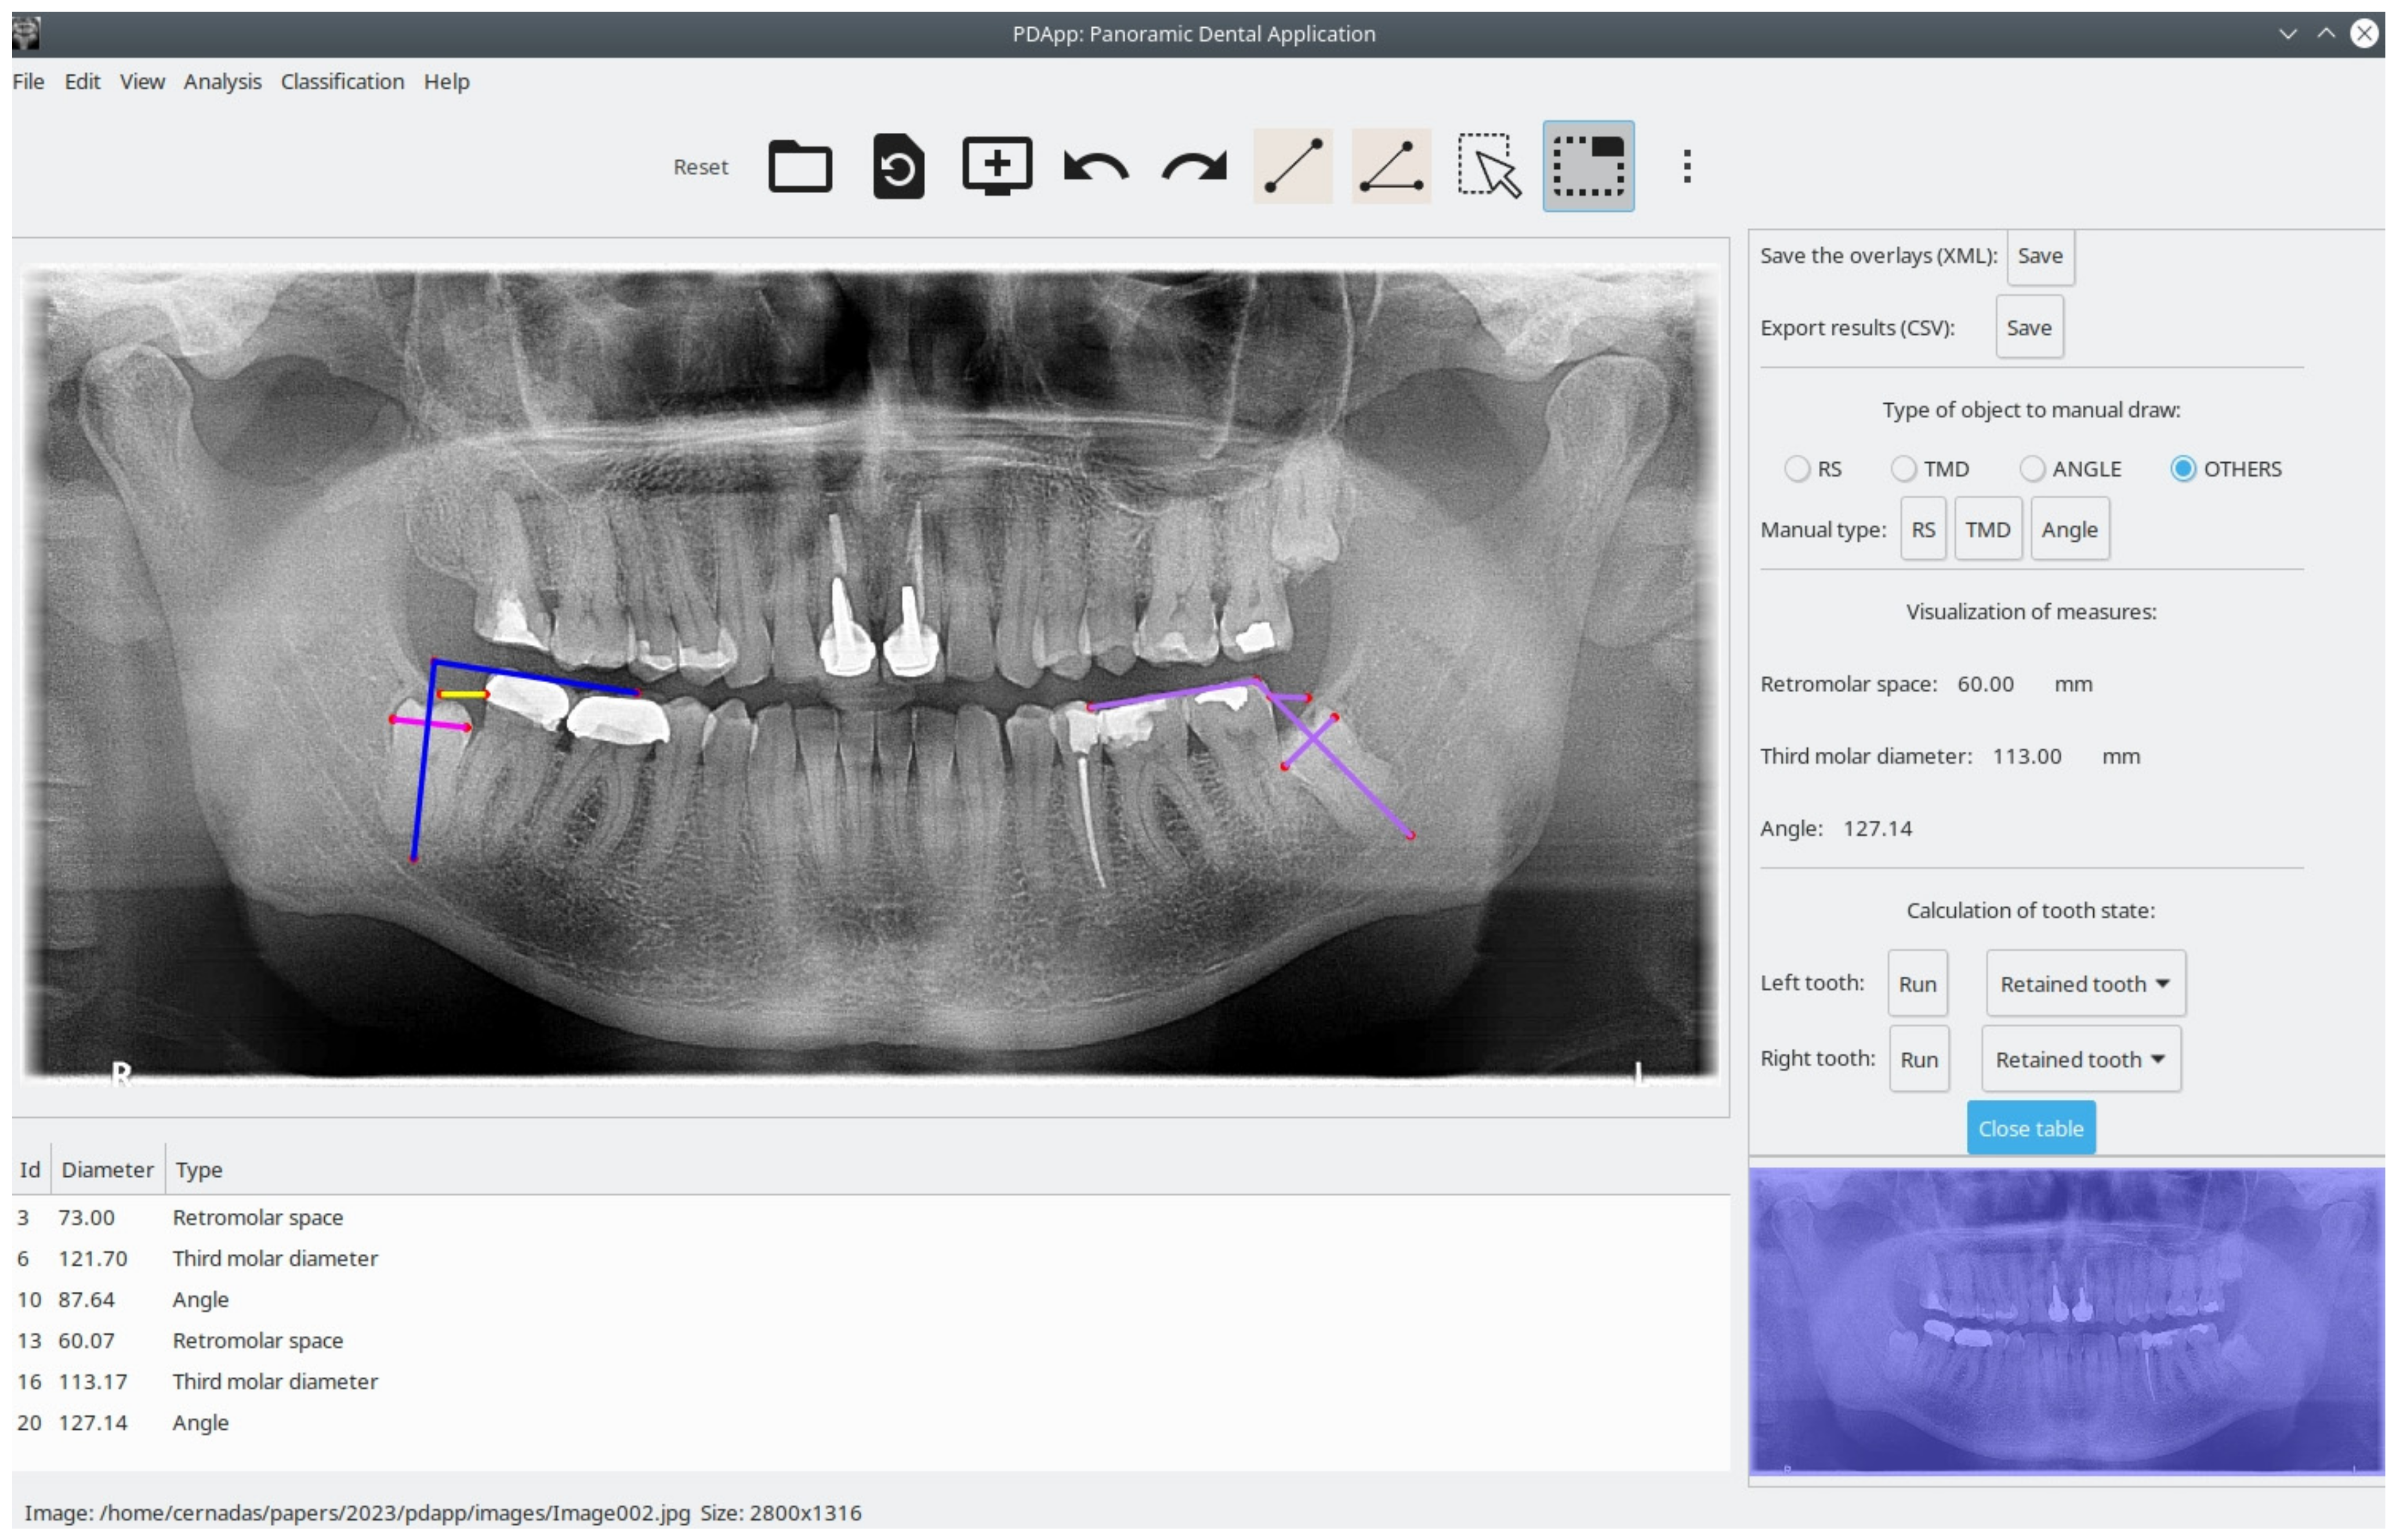

To evaluate PDApp based on operation in a real environment, the software was installed at the dental clinic of the Dentistry School of Medicine and Odontology of the University of Santiago de Compostela (Spain) in February 2021. Dental experts then used PDApp in their daily work to analyze images, which required that they manually draw the retromolar space and the third molar diameter and angle. PDApp then automatically classifies the third molars in radiological images as erupted or retained. Their operations using PDApp were logged into XML files for later statistical evaluation of the machine learning algorithm (SVM classifier) incorporated in the software. We used accuracy (rate of third molars correctly classified by the software) as a measure of the classifier performance. As mentioned, the classifier included in PDApp was initially trained using a dataset of 188 molars. Thereafter, PDApp was used to classify 539 third molars from 289 patients, and 97.96% of third molars were correctly classified. Figure 3 shows an example of correct classification of the third molar by PDApp as retained. Figure 4 shows a case of a third molar that is classified as erupted by PDApp.

Figure 3. Visual example showing two third molars analyzed, in which the PDApp prediction for both cases is correct as a retained tooth. The pink line represents third molar diameter, the yellow line represents retromolar space, and blue lines represent the angle of eruption. The lateral panel shows the measures for the left third molar (violet lines on the image represents the measurements realized).